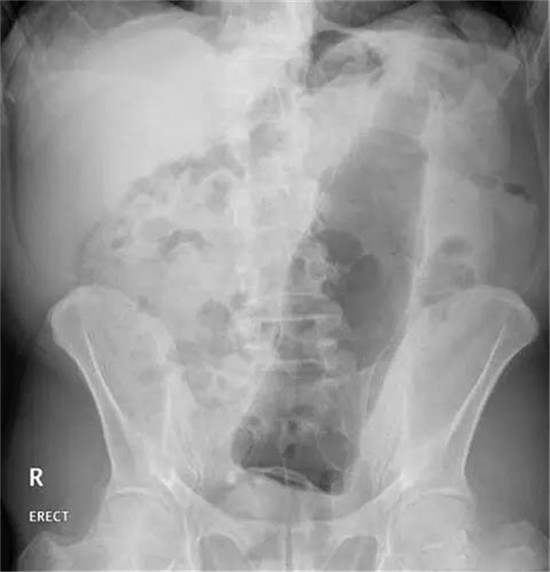

第4天,他拉不出大便。剧烈呕吐,剧烈腹痛。实在熬不住了,就去了一个大医院,但是,他隐瞒了自己把黄鳝塞进菊花的病史。

医生给他检查的时候,发现已经有腹膜炎症状,怀疑肠梗阻,拍了个片子,就是上面那个片子:一条大黄鳝在肚子里。

考虑到他已经有腹膜炎的症状,说明肠子已经有个地方破了。只能动手术了。

把肚子打开后,发现大肠破了个洞,黄鳝的头,就在那个洞里。他肚子里都是大便。他的肠子水肿很厉害。黄鳝堵住了大肠,肠梗阻,导致大肠坏死穿孔了。

这种情况下,就是把大肠的洞补起来,洞也长不好。只能造瘘了。也就是在破了个洞的地方把大肠割断,肚皮上挖个洞,大肠拖到肚皮外面,以后的大便从肚皮上排出来。等肚子里炎症消退后,再把大肠放回肚子里接回去。这样他要动2次手术。

就这样,他死里逃生了。